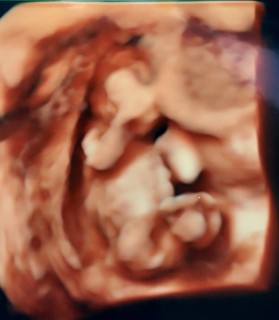

このあと4Dに切り替えてくれましたが

終始後ろ向きでした(>_<)

先生曰く、この時期のあかちゃんは大体後ろ向きだそうで、きっとまだ超音波に慣れてないからとの事でした!

次回の検診ではこっちを向いてくれる事が多いそう!楽しみ~